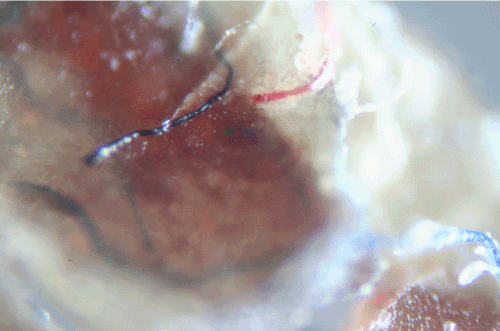

Biopsies from late proliferative stage BDD lesions were examined microscopically for comparison (Figures 5A-5D). Although the scale of filaments was much larger, the BDD filaments (roughly ten times larger) were similar in appearance compared to the specimens observed in Case 1 (Figure 5A, Figure 5B). Filaments were macroscopic, opaque and dirty white in color, ranging in size from less than 0.5 mm in diameter to about 1 mm in diameter. In cross section filaments appeared to originate beneath the stratum corneum (Figure 5C). Longer filaments were close to 1 mm in length. The BDD filaments demonstrated fluorescence under UV light (Figure 5D).

Figure 5C: Cross section of BDD sample showing coarse fibers that originate beneath the stratum corneum (8x magnification).

Figure 5D: BDD sample showing coarse fibers with fluorescence under UV lighting (8x magnification).